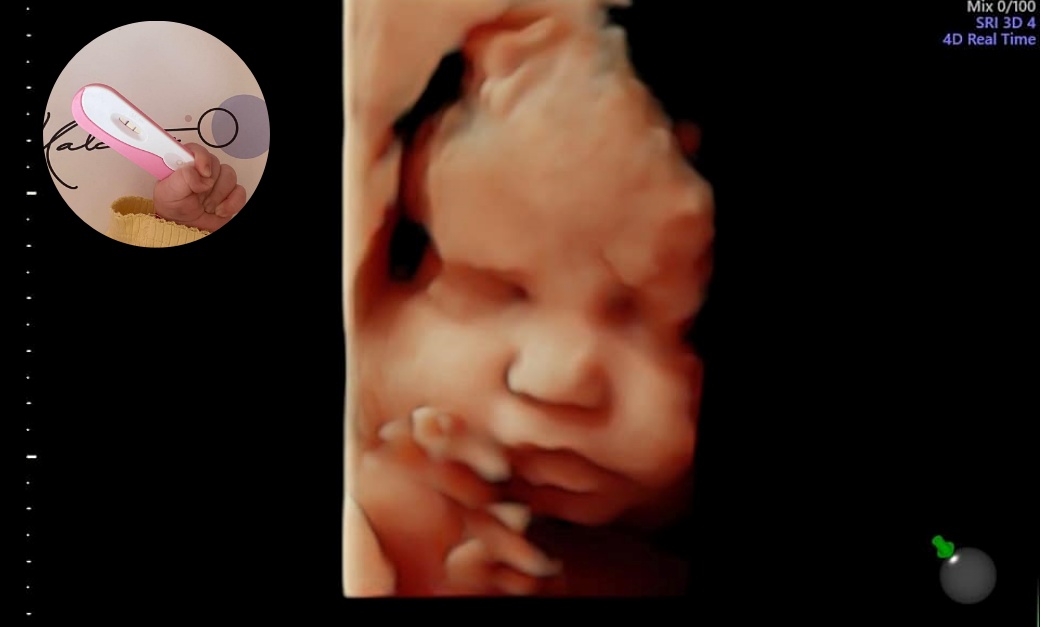

Третата ни среща с доктор Калчев беше на 31.05.2022г., когато вече на ехографа се виждаше мъничка точица и се чуваше сърчице. Отново онази приятелска обстановка и чувство на спокойствие. Отново чухме точно това, от което имахме нужда: “Това е нашето бебе и всичко ще е наред. Искам да сте спокойни!”

На 10.01.2023г., точно година след първото ни посещение в МЦ д-р Калчев, на бял свят се появи нашата първородна дъщеричка.